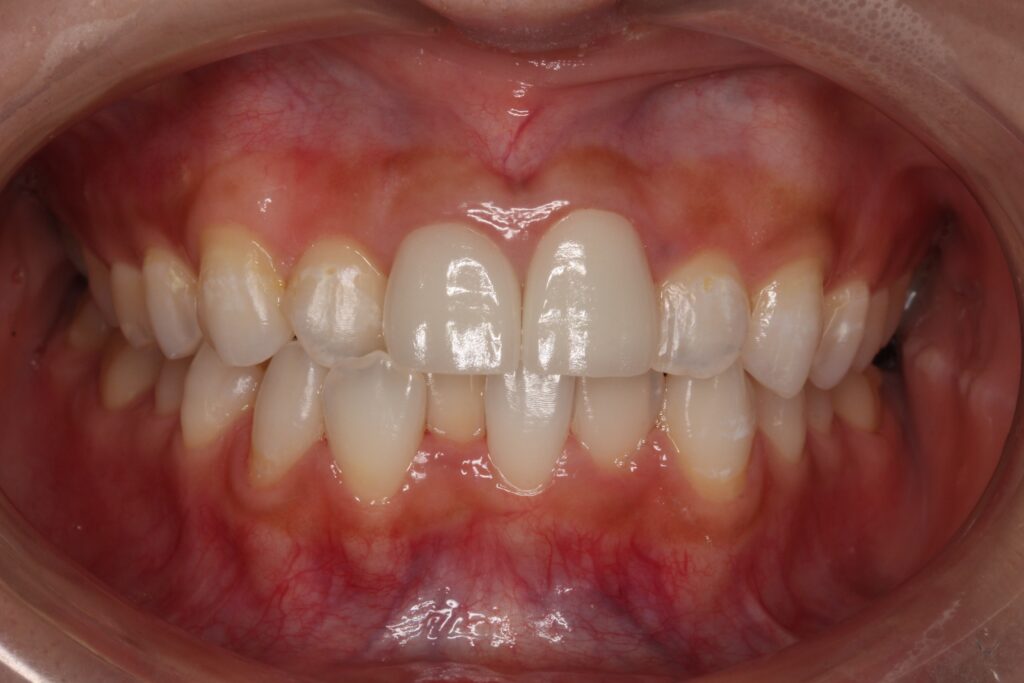

治療後の写真です。

メタルタトゥー黒い歯肉が無くなりました。

今回はメタルタトゥーの除去と、

レジン前装冠をセラミックへの交換。

ホワイトニングを行っています。

同じ方のお口の中とは思えないですね(*_*;

ホワイトニングをしたことによっても全体的に明るくなりました。